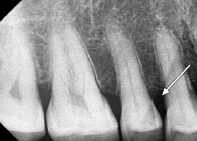

28. What is showing by arrow?

29. What is shown by the arrow?